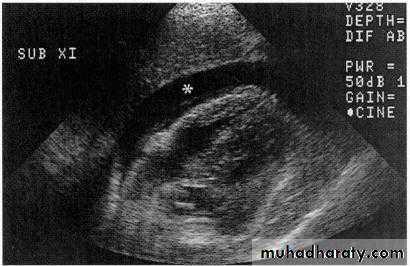

Focused Abdominal Sonography for Trauma FAST

• Detects free fluid in the peritoneal cavity. Non invasive and

rapid. 88% sensitive,99% specific and 97% accurate

• Demonstrate presence of free intraperitoneal fluid

• Evaluate solid organ hematomas• Advantages

• No risk from contrast media or radiation

• Rapid results, portability, non-invasive, ability to repeat exams.

• Disadvantages

• Cannot assess hollow visceral perforation

• Operator dependent

• Retroperitoneal structures are not visualized

FAST

Four View Technique:Morrison’s pouch (hepatorenal)

Douglas pouch (retropelvic)

Left upper quadrant (splenic view)

Epigastric (View pericardium)